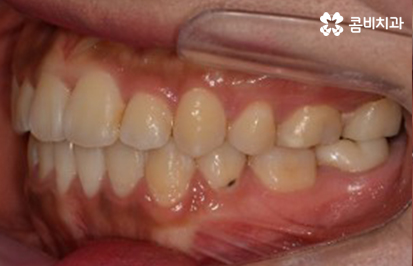

유지 장치가 부착되어 있는 모습

가지런 치열과 하얀 치아의 모습은 건강함의 상징이 되기도 하고

인상에도 많은 영향을 주는 만큼 장치를 풀어낸 후에는

미백 치료를 함께 받으시는 분들도 많습니다.